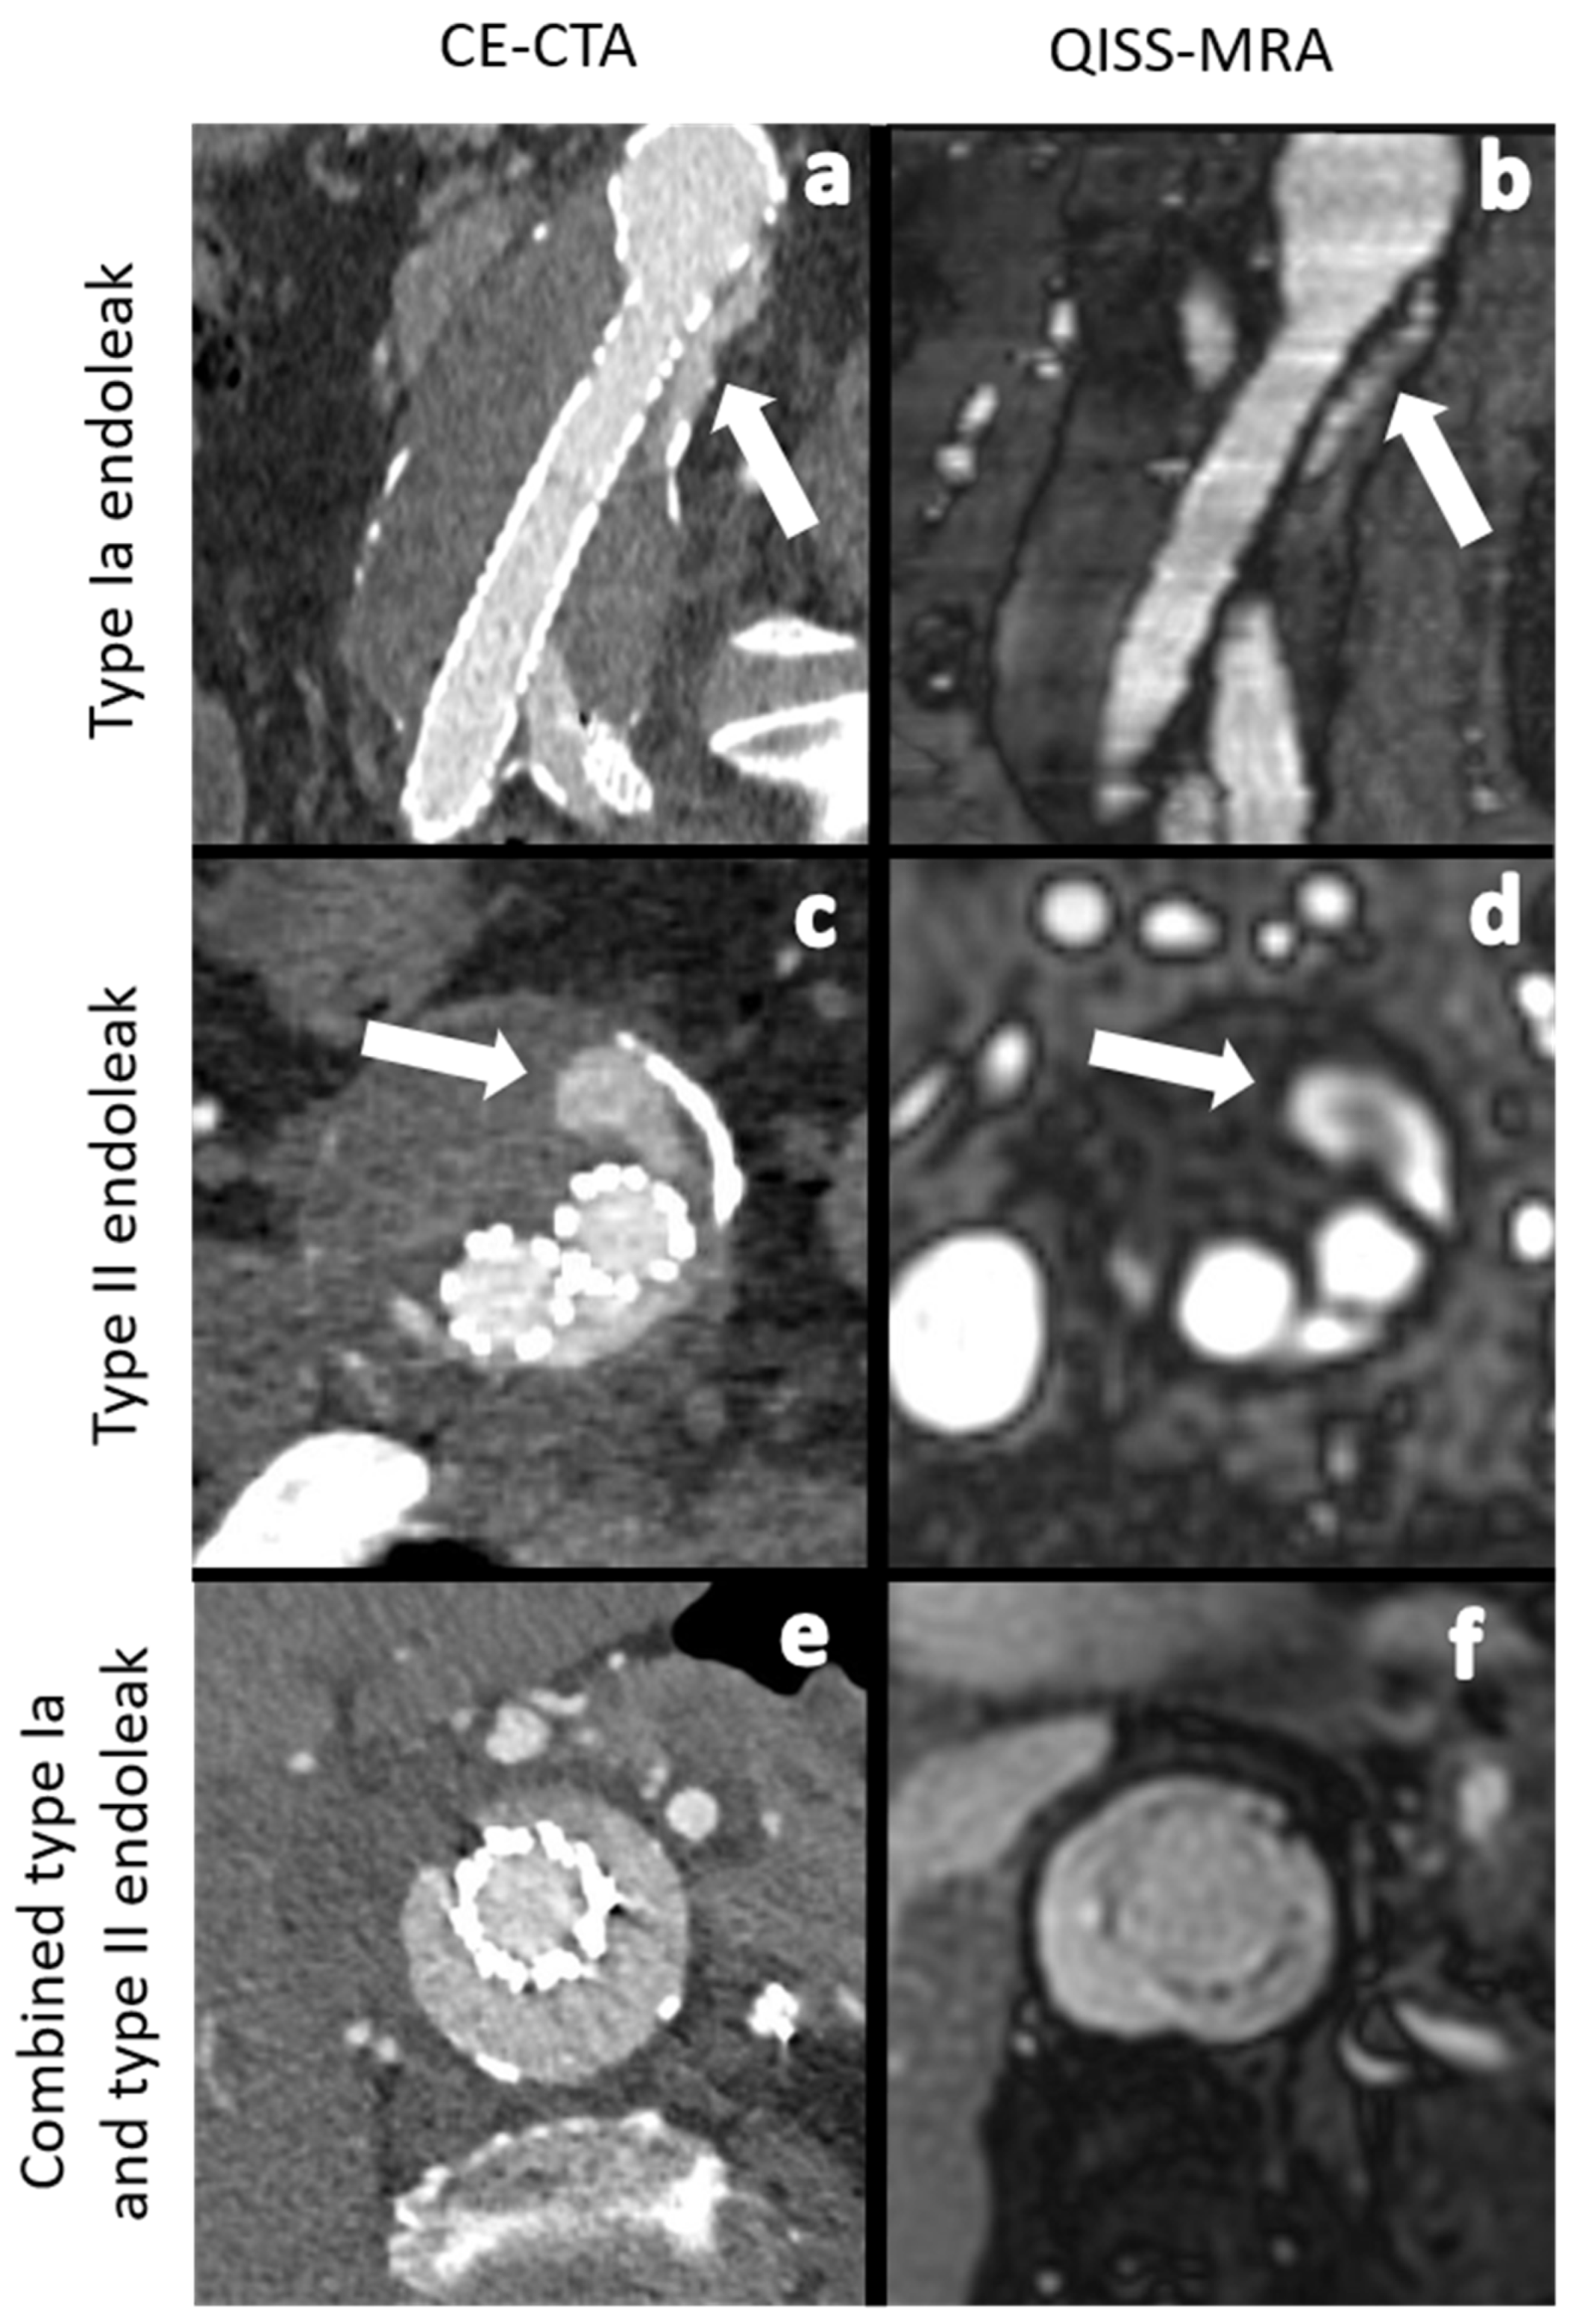

| Type Ia | 1 (6.2%) | 1 (8.3%) | 1 | Type Ia | 1 (7.1%) | 1 (9.0%) | 1 | ||

| Type Ib | 3 (18.7%) | 3 (25.0%) | 1 | Type Ib | 3 (21.4%) | 3 (27.0%) | 1 | ||

| Type II | 11 (68.7%) | 8 (66.7%) | 0.71 | <0.01 | Type II | 9 (64.2%) | 7 (63.6%) | 0.79 | <0.01 |

| Type III | 0 (0%) | 0 (0%) | Type III | 0 (0%) | 0 (0%) | 1 | |||

| Type V | 1 (6.2%) | 0 (0%) | Type V | 1 (7.1%) | 0 (0%) | ||||

| Total number | 16 | 12 | Total number | 14 | 11 | ||||